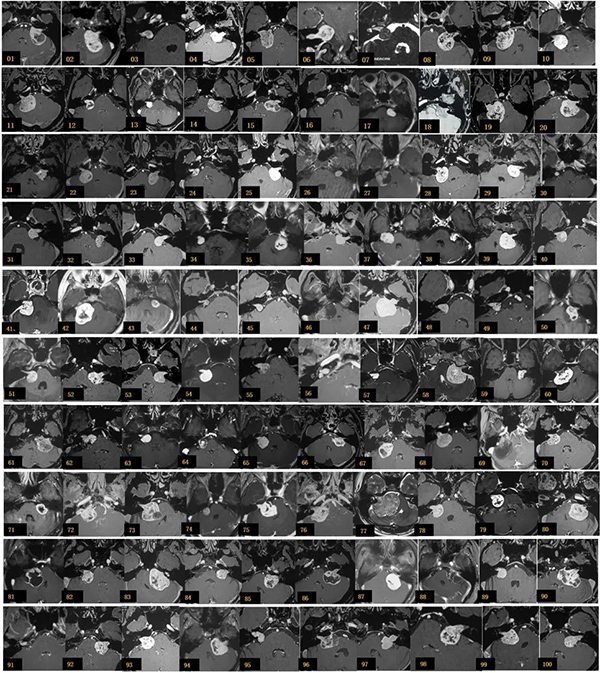

2018.12-2019.8   完成的100例听神经瘤手术